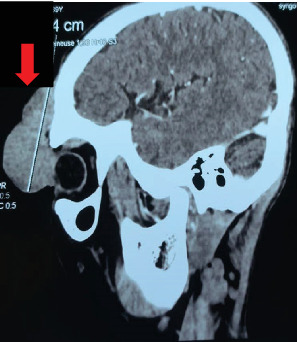

隆突性皮肤纤维肉瘤(DFSP)是一种罕见的软组织肉瘤,起源于真皮结缔组织中的成纤维细胞,约占所有软组织肉瘤的1%。虽然大多数病例累及躯干和四肢,但只有10%-15%发生在头侧区域,占所有头颈部肿瘤的不到1%。DFSP因其在手术切除后局部复发的高倾向和低转移潜力而值得注意。我们报告一例复发性前额DFSP延伸至左额窦前壁,未累及大脑,患者为33岁男性,既往有三次大面积局部切除史。一个多学科的癌症小组推荐全身伊马替尼治疗。本病例强调了在不寻常的地点管理DFSP的挑战,强调了多学科方法在解决复发性和复杂表现方面的重要性。

Dermatofibrosarcoma protuberans (DFSP) is a rare soft tissue sarcoma originating from fibroblasts in the dermal connective tissue, comprising approximately 1% of all soft tissue sarcomas. While most cases involve the trunk and extremities, only 10%-15% occur in the cephalic region, representing less than 1% of all head and neck neoplasms. DFSP is notable for its high propensity for local recurrence following surgical excision and its low metastatic potential. We report a case of recurrent DFSP of the forehead extending to the anterior wall of the left frontal sinus, without brain involvement, in a 33-year-old male with a history of three prior wide local excisions. A multidisciplinary cancer team recommended systemic imatinib therapy. This case highlights the challenges of managing DFSP in an uncommon location, underscoring the importance of a multidisciplinary approach in addressing recurrent and complex presentations.